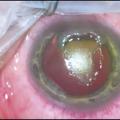

– des papilles géantes, tarsales supérieures surtout (fig. 3) ;

– des grains de Trantas limbiques : amas superficiels blanchâtres d’éosinophiles, au niveau du limbe, qui ressemblent à des grains de mil (fig. 4).